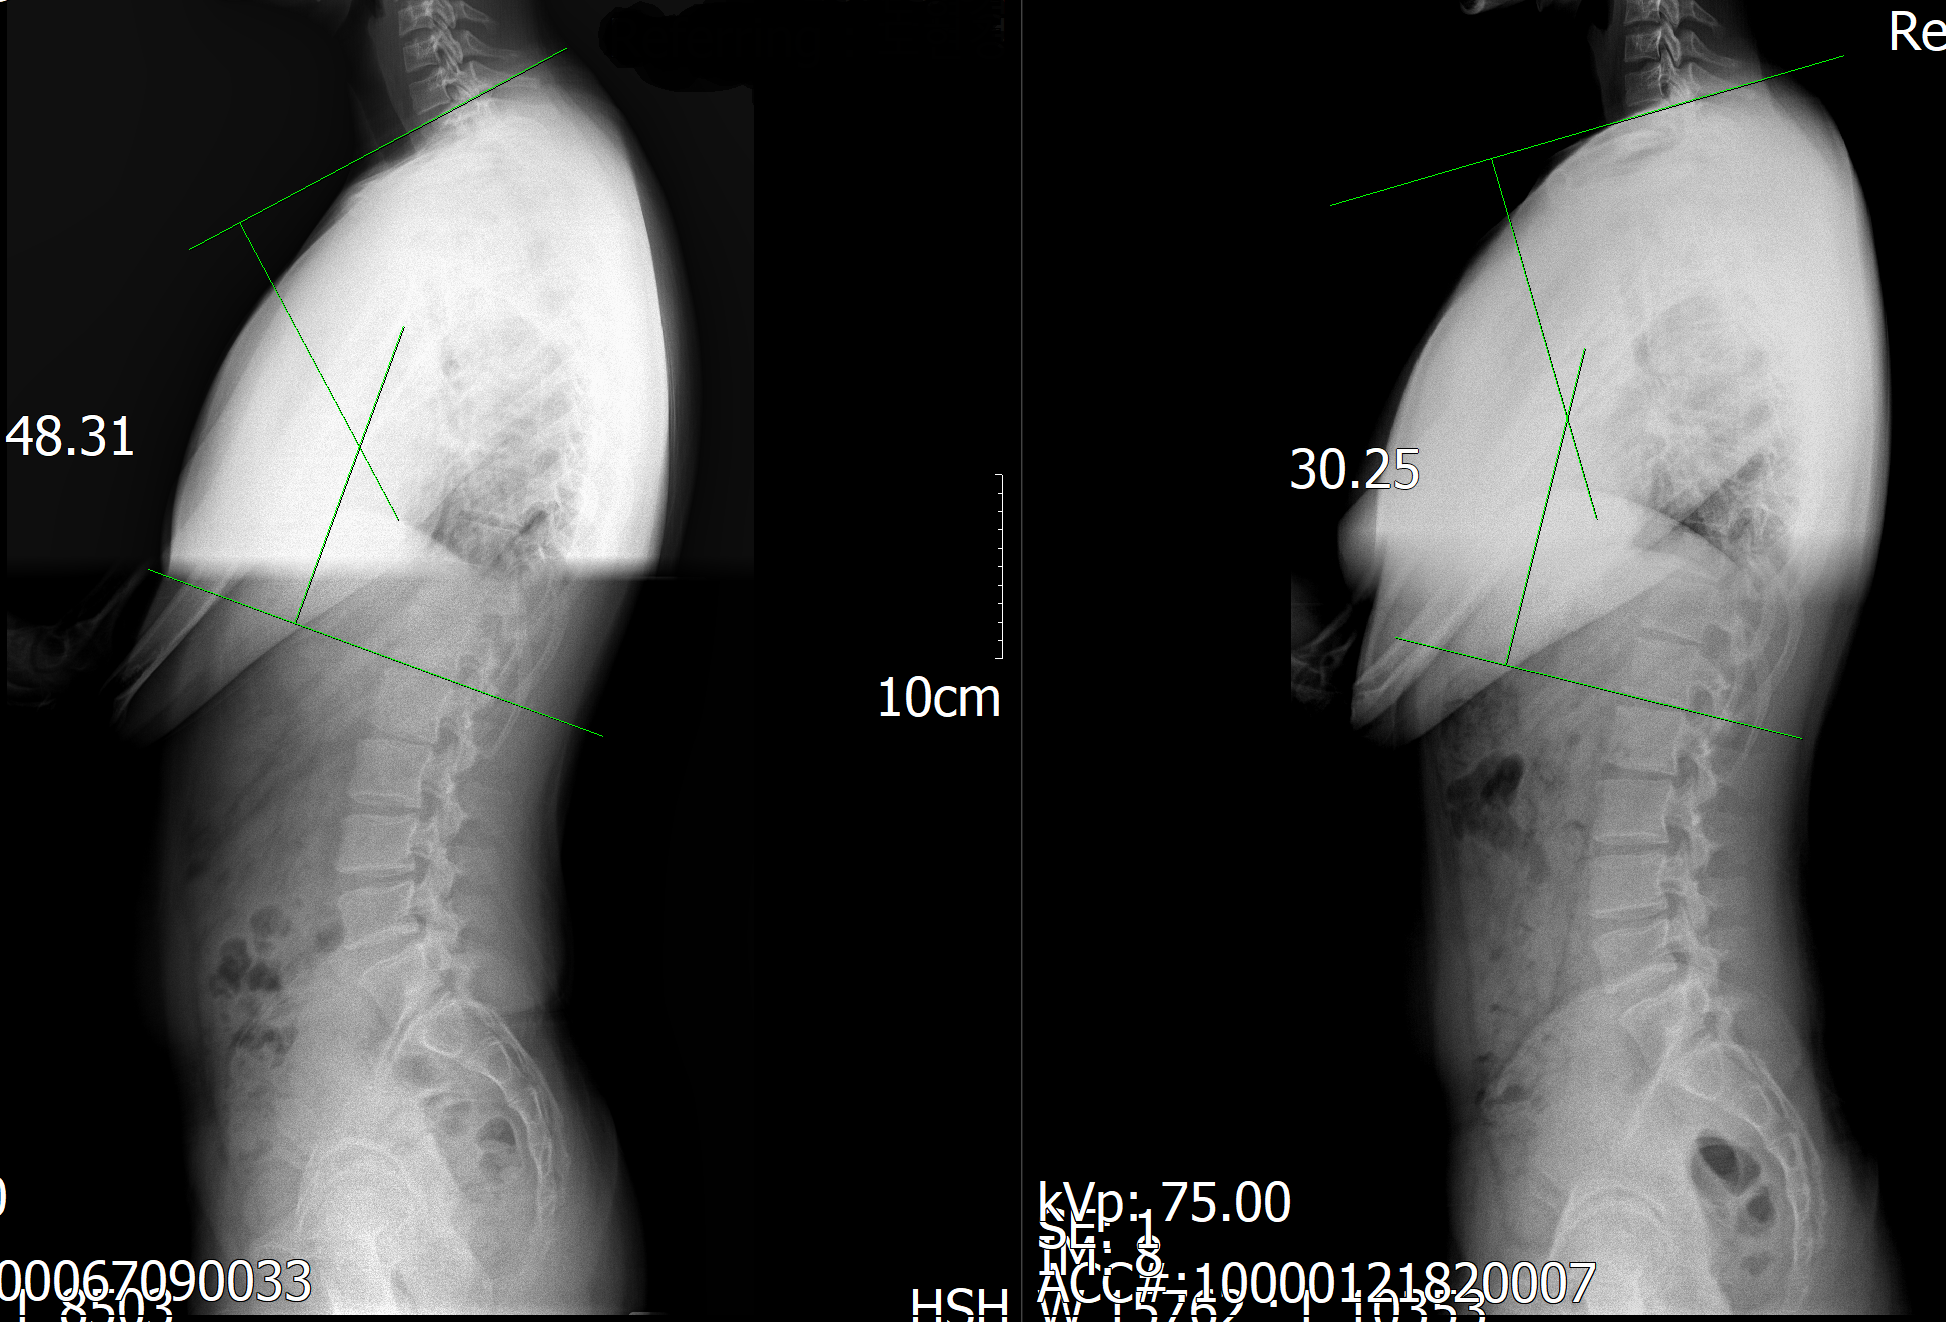

거북목, 굽은 등, 골반 틀어짐, 척추측만증… 이제 더 이상 혼자 끙끙 앓지 마세요! 올곧체형교정센터에서는 3D 체형 분석과 1:1 맞춤 재활 운동 프로그램으로 여러분의 몸을 바르게 세워드립니다. 지금 네이버 예약하면 ‘3D 체형 분석 + 기능적 평가’ 무료 상담까지 받을 수 있으니 놓치지 마세요!